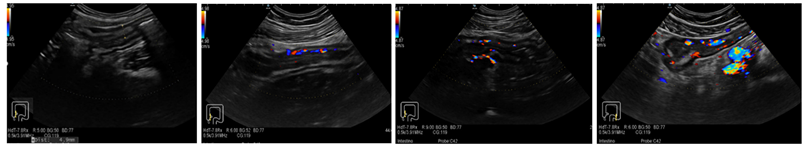

3.1. Ultrasound Features of CD

| Grade 1 | Grade 2 | Grade 3 | Grade 4 |

| No vascularization signal at color Doppler | Mild: minimal signal, short stretches of vascularity in spots | Moderate: longer stretches of vascularity, blood vessels located only intra-mural | Severe: long continuous intra- and extra-mural blood vessels, extending into the mesentery |